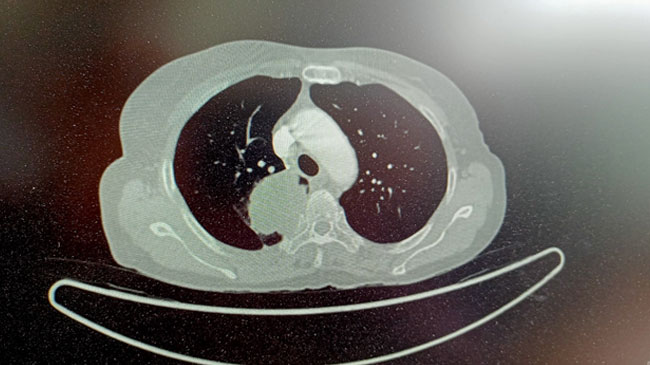

55-year-old women presented with complain of bleeding per vagina for which She was evaluated and diagnosed in December 2018 as squamous all carcinoma cervix STAGE III. She received definitive chemoradiation 46GY/ 23# with concurrent chemo 5 cycles weekly carboplatin under AUC 2 from 18/12/18 to 31/01/2019 followed by ICBT. She was on regular follow up till December 2020. Later she presented with Complaints of upper back pain. She was evaluated for the same. CT Thorax suggestive of right upper lobe lung mass. PET-CT suggestive of metabolically active soft tissue density lesion measuring 67 x 42 x 61 mm involving apical / posterior segment of right Lung upper lobe causing lytic distraction of D2/ D3 vertebrae and right 3rd & 4th rib, extending into spinal canal with thecal sec compression, few lymph nodes at mediastinal station, without metabolic activity, bilateral lung nodules with few of them slowing increase metabolic activity. No definitive scan evidence metabolically active, residual/ recurrent disease at treated bed site in cervix region. CT guided lung biopsy done 06/01/2021. Biopsy suggestive of squamous all carcinomas, IHC → Positive for p16& p40, Negative for TTF- 1 & diagnosed as 2nd primary Carcinoma Lung STAGE IV. She received systemic chemotherapy Paclitaxel 175mg/M2 & carboplatin AUC 5 every 3 weekly for 6 cycles and completed treatment on 26/05/2021. Follow- up CT thorax at the end of 1 Month shows Homogenously enhancing soft tissue thickening, measuring 16x33mm is noted in apical with posterior segment of right upper lobe with sclerosis & erosion of adjacent posterior segment of 3rd, 4th rib. Now she is improved clinically & radiologically with treatment.